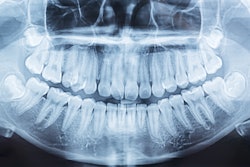

Recent artificial intelligence (AI) models have shown to accurately identify dental diseases from dental panoramic radiography (DPR) images, suggesting they may improve diagnosis and patient outcomes. This review was published on June 21 in Evidence-Based Dentistry.

AI detected caries and periodontal bone loss, and identified and numbered teeth with high accuracy, and other conditions with high sensitivity and specificity, wrote author, Dr. Manas Dave, of the University of Manchester School of Medical Sciences in the U.K.

The analysis revealed that AI models were highly accurate in detecting periodontal bone loss (93%), teeth identification and numbering (93.6%), caries (91.5%), and maxillary sinusitis (87.5%). Furthermore, AI detected periapical lesions with high sensitivity (99.9%) and specificity (92%), Dave wrote.